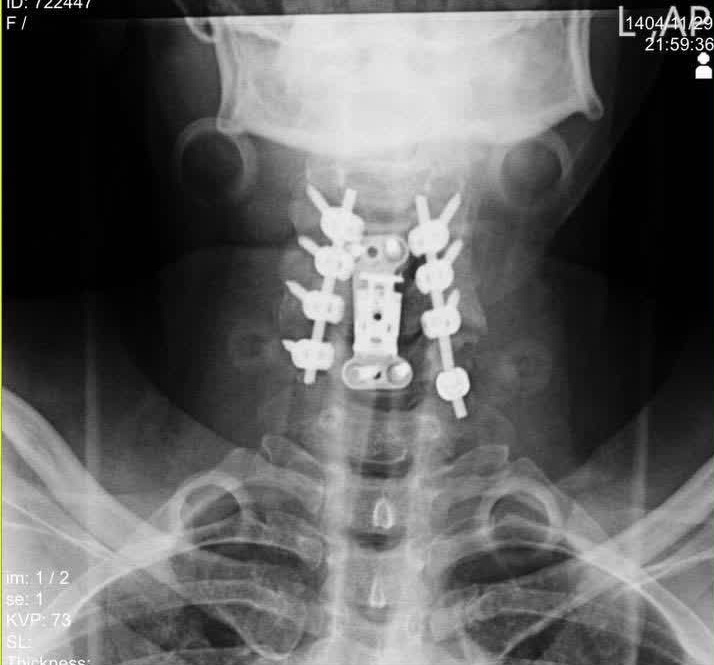

دکتر محمدی ادامه داد: ۷۲ ساعت پس از جراحی اول، بیمار مجدداً به اتاق عمل منتقل شد. در مرحله، تیم جراحی با انجام «لامینکتومی» از مهره سوم تا ششم (C3-C6)، فشار را از روی بخش پشتی نخاع برداشتند و با استفاده از سیستم «پیچ و راد» (Screw and Rod) در ۸ نقطه مختلف، پایداری کامل ستون فقرات بیمار بدست آمد.